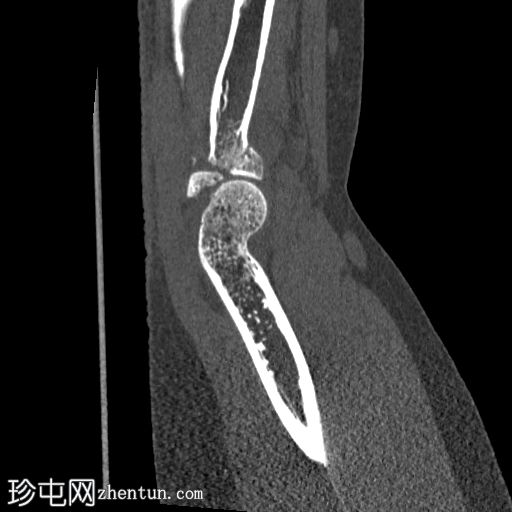

冠状面骨窗

显示整个桡骨头粉碎性骨折,特征为两个以上大骨折块,以及倾斜且受压的关节节。

这表明该骨折为不稳定骨折,根据Mason桡骨头骨折分型,为IIIC型。

远端肱骨和可见尺骨未见骨折征象。

此外,由于关节积血导致关节扩张,肘关节脂肪平面弯曲。